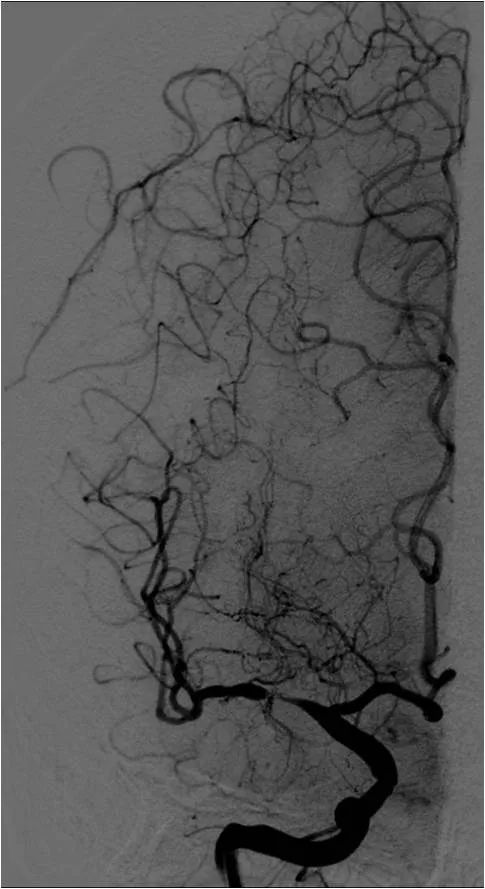

DSA:右大脑中动脉M1段重度狭窄,后循环向前循环代偿欠佳(图7-10)。

图7

图8

图9

图10